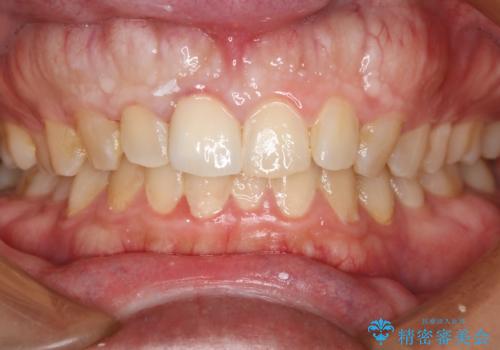

前歯が綺麗になったと大変満足して頂けました。